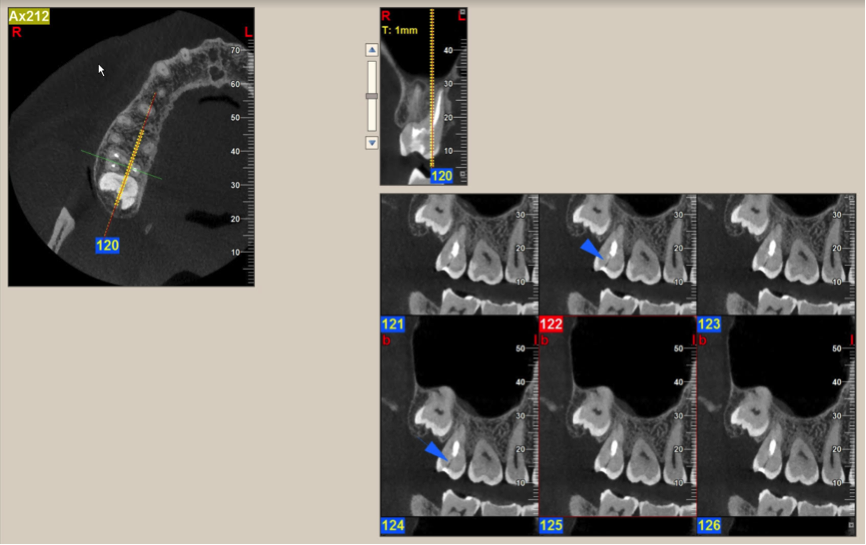

Other kinds of artifacts that are related to the CBCT technology itself may be present and compromise image quality, sometimes rather significantly.7 These artifacts are an inherent problem of CBCT and medical computed tomography because their appearance is a product of the reconstruction algorithms employed to compose the digital CBCT and CT images. In addition, the presence of any radiopaque materials is a frequent cause of artifacts. Metallic dental restorations, fixed prostheses, posts, and even gutta-percha may create artifacts that can obscure the visualization of the region of interest (Figure 3). As a result, fine diagnostic tasks may be impossible in proximity to restorations with high radiopacity. A number of CBCT manufacturers currently offer artifact reduction applications. These seem to have improved the resulting image quality; however, any possible gain in diagnostic efficiency has yet to be determined (Figure 4).

(3.) A CBCT coronal section of the maxillary sinuses showing severe metallic artifacts (horizon- tal, bright in appearance bands) originating from the crowns of the maxillary and mandibular teeth.

Figure 3

(4.) When compared to the original CBCT image (left), the application of artifact reduc- tion algorithms have improved the visualization between the two dental implants (right image).

Figure 4